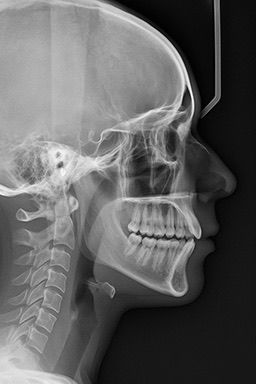

Radiografía cefalométrica (lateral con trazado)

Imagen lateral de la cabeza con trazados cefalométricos que permite evaluar dientes, mandíbula y estructuras craneofaciales para diagnóstico y planificación de tratamientos dentales y ortodónticos.